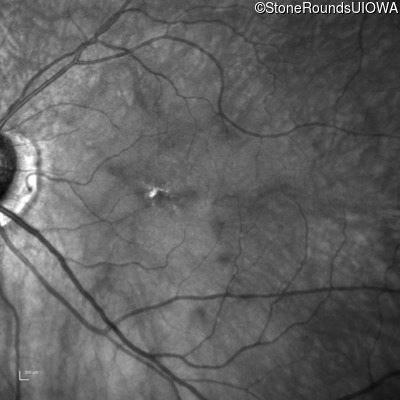

Infrared Fundus Photograph - Right - 20/200

Exemplar